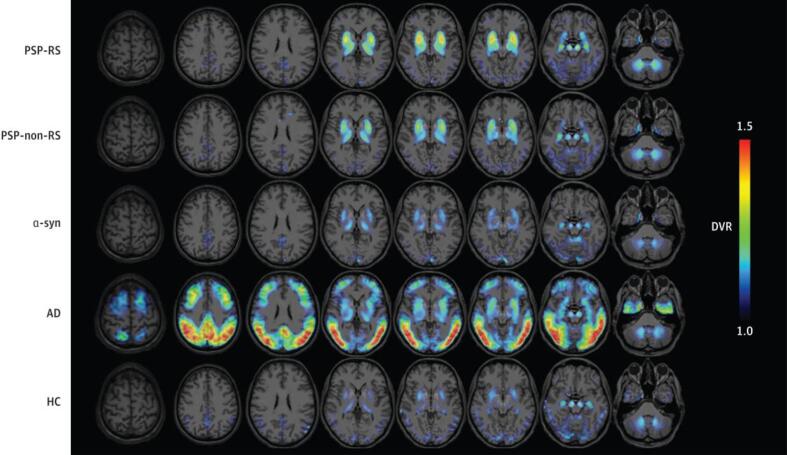

| Brendel (2020) | [18F]PI-2620 | 40 PSP-RS, 20 PSP-non-RS, 10 alpha-synucleinopathies, 10 AD, 10 HC | Increased binding in PSP target regions compared to control groups; region with best discriminatory ability was globus pallidus internus |

Although this tracer’s concentration and stability is lower in 4R tauopathies, [18F]PI-2620 does appear to be a promising tracer for distinguishing parkinsonisms with improved accuracy. For instance, [18F]PI-2620 uptake is asymmetric in the pallidum of CBD patients compared to PD and PSP patients ref. [81]. Furthermore, this tracer has the potential for great clinical utility in monitoring CBS disease progression because the hemispheric lateralization of [18F]PI-2620 is associated with the contralateral manifestation of disease severity ref. [82]. In terms of PSP, Brendel et al ref. [83] demonstrate [18F]PI-2620′s utility in facilitating more reliable diagnoses of this disorder. In their study, they use DVR measurements and autoradiography to show that this tracer is effective in differentiating PSP from alpha-synucleinopathies (e.g., PD), AD, and controls with 85 % sensitivity and 77 % specificity (Fig. 5). Consistent with previous literature, the region with the most significant difference is the globus pallidus internus in PSP patients compared to controls.